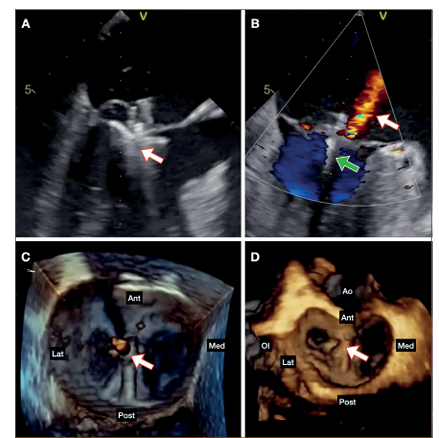

https://www.youtube.com/watch?v=gKopeZK-m2oSe discute el caso en heart team y por el elevado riesgo quirúrgico no se plantea cirugía convencional. Dada la factibilidad anatómica para realizar una reparación percutánea con técnica borde a borde, se opta por esta estrategia. El procedimiento se realiza bajo anestesia general, intubación orotraqueal y monitorización ecocardiográfica transesofágica continua. A través de un acceso venoso femoral derecho se realiza punción transeptal ecoguiada y mediante guía fluoroscópica y ecocardiográfica se implantan dos dispositivos MitraClip® (XTR y NT) a nivel de los festones A2-P2 de la válvula mitral (figuras 2 y3, video 2A). El ecocardiograma post implante (video 2 B y C) evidencia insuficiencia mitral remanente leve y gradiente transmitral no significativo (2 mmHg).

Figura 2 Ecocardiograma transesofágico intraprocedimiento. A: 120 grados, posicionamiento del primer clip (flecha) y enganche de los velos. B: Doppler color, insuficiencia mitral residual (flecha blanca) luego de implante del primer clip (flecha verde). C: 3D (“vista de cirujano”), resultado luego de liberación del primer clip (flecha). D: 3D (“vista de cirujano”), resultado final luego de implantado segundo clip (flecha).